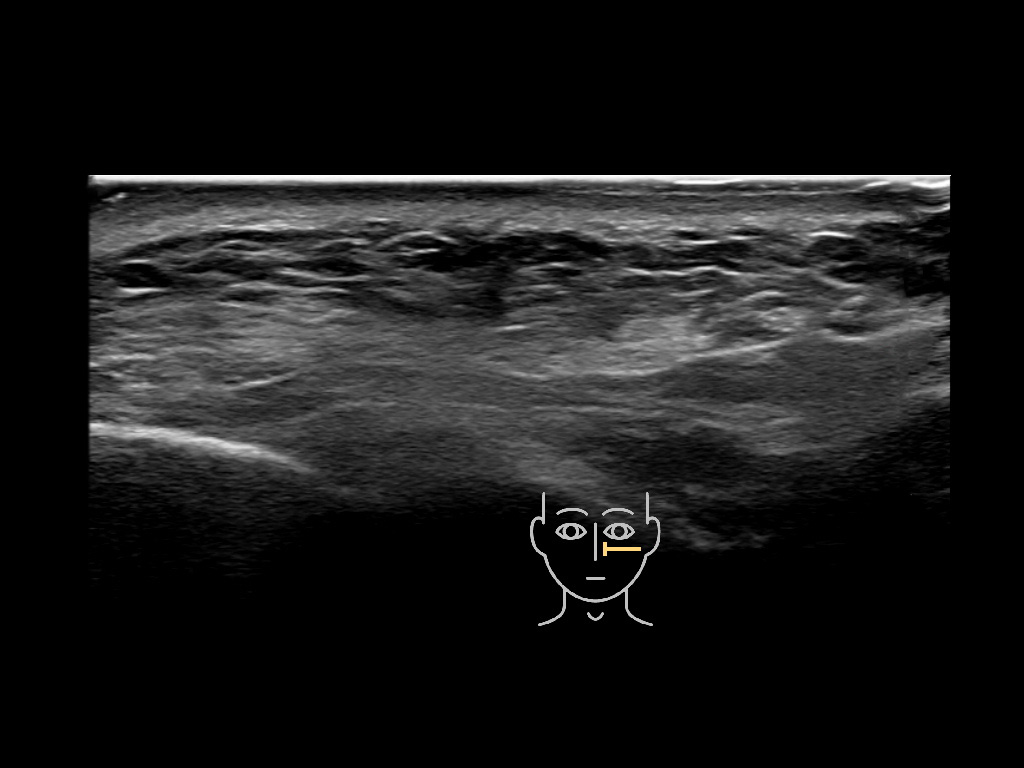

Filler deposits may end up unintentionally in the SMAS or fascial layers of the skin. Very often this will not lead to adverse events, however, adverse events ( nodules, migration / redistribution impaired muscle movement and smiling and malar edema) are are often related to filler ending up in the SMAS or fascia.

Study the first image to recognize the different layers. If you are sure about the layers, swipe to the second image to view the answer (if applicable).